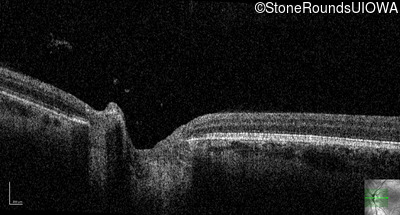

Optical Coherence Tomography - Left - 10/200 sc

Exemplar / OCT Stack